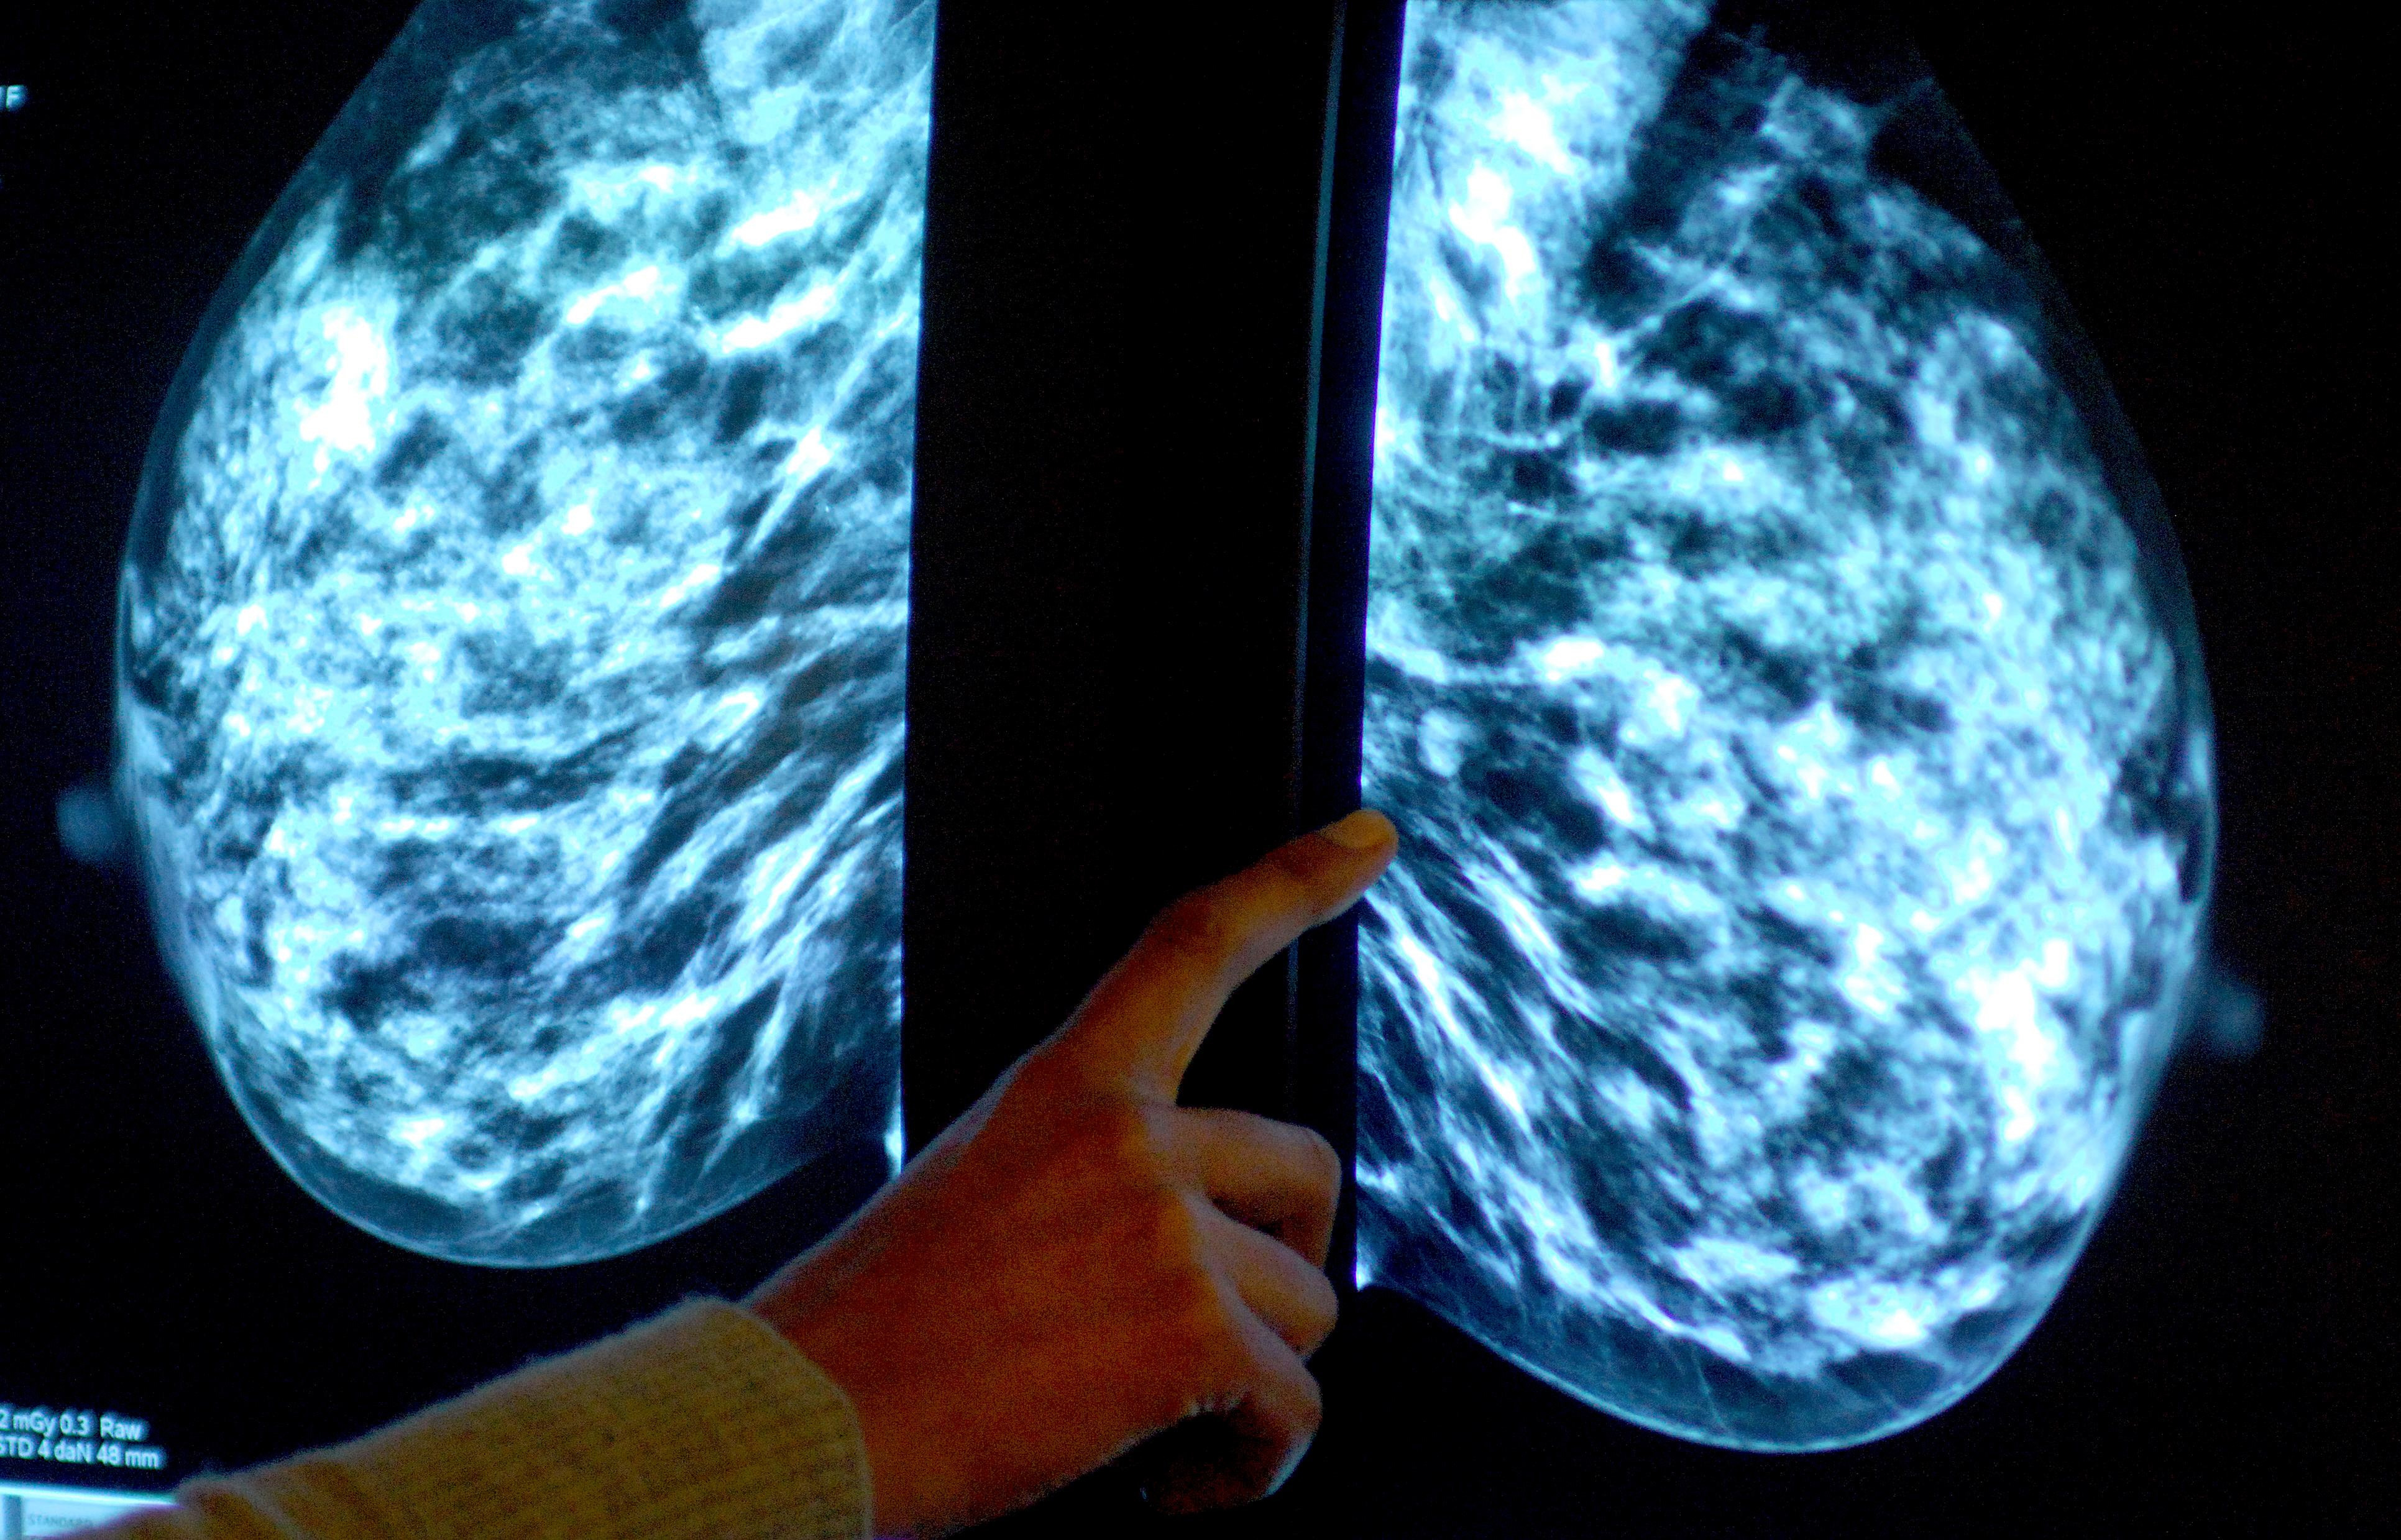

Breast screening uptake in Devon remains below pre-pandemic levels, new figures show.

It comes as charities have said women still face too many barriers to regular testing, as fewer people in England underwent tests than before the coronavirus pandemic